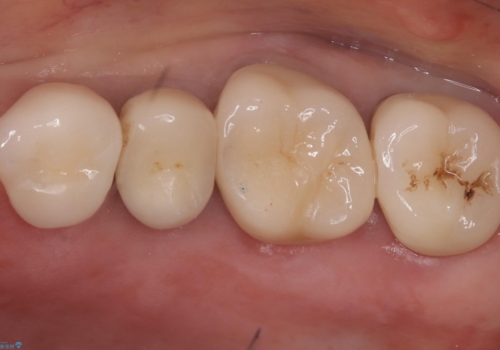

古いクラウンを除去し、不適部位から中で広がっていたカリエスを除去したのちCRにて築造、仮歯を経てセラミッククラウンをセットしています。